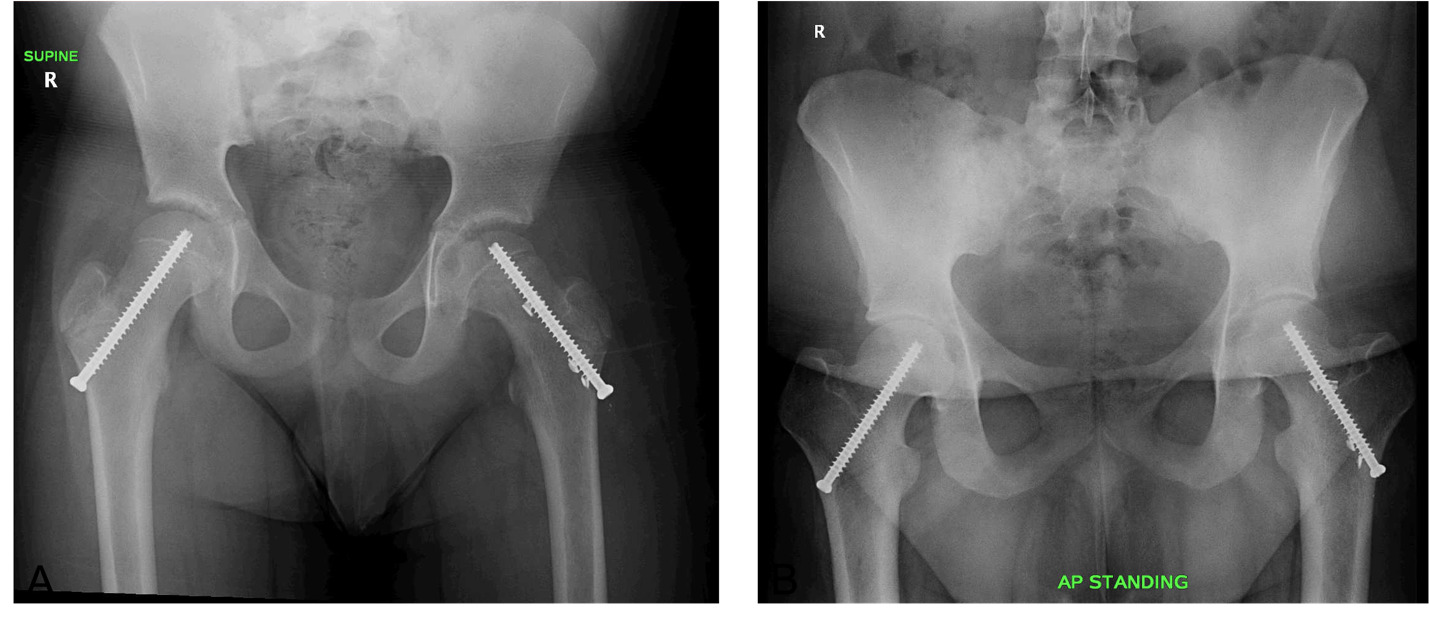

Here we have an individual who underwent prophylactic pinning, the left image showing the individual immediately following initial pinning with the final follow up on the right. This is a left-sided SCFE that underwent in situ pinning and was subsequently prophylactically pinned on the right side. When comparing the right proximal femur at these two timepoints, there is a relative loss of femoral neck length and femoral head-neck offset, in addition to an increase superiorly in the relative position of the greater trochanter to the center of the femoral head.